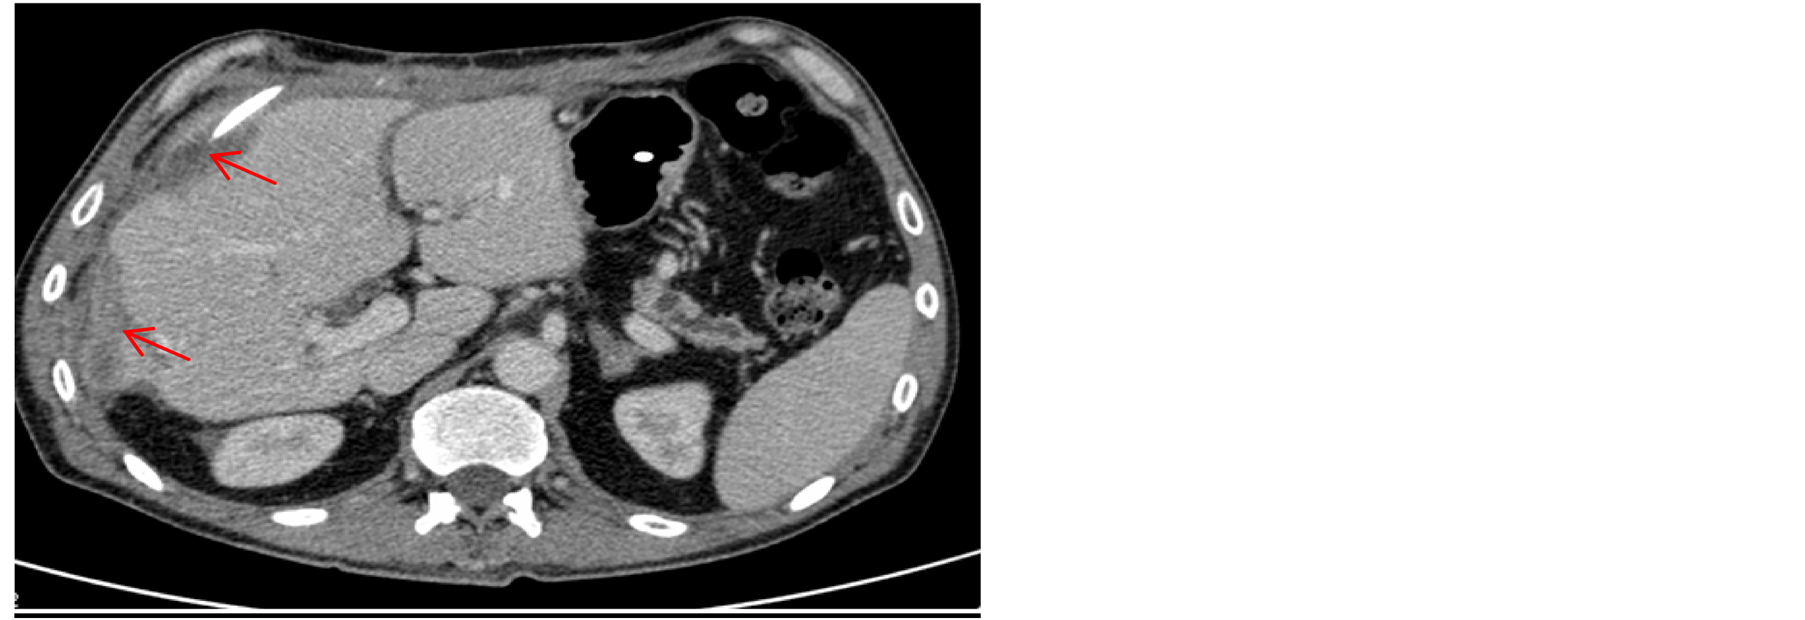

instability, selective embolization of right hepatic artery was performed, without any clear radiological improvement. Owing to further clinical deterioration, urgent surgical evacuation of the hematoma had to be undertaken 72 hours after the ERCP. In the postoperative period the patient presented infection of the collection, which indicated colocation of percutaneous drainage (Figure 3), and broad-spectrum intravenous antibiotics were administered over a period of six weeks. The patient gradually recovered and complete resolution of hematoma was seen in control CT scan, it being thus possible to withdraw the drainage catheter (Figure 4). He was discharged two months after admission in good condition.

Figure 4. Resolution of voluminous hepatic hematoma observed on abdominal CT scan.